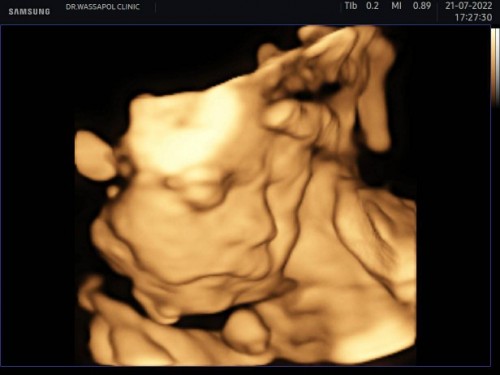

อัลตร้าซาวด์4มิติวันนี้

ลุ้นมากค่ะ กลัวน้องนอนคว่ำ สุดท้ายก็ได้เห็น เด็กน้อย 27วีคจร้า เป็นเพศชายคร้าบแม่ๆ

จมูกน้องโด่งมากเลย🥰